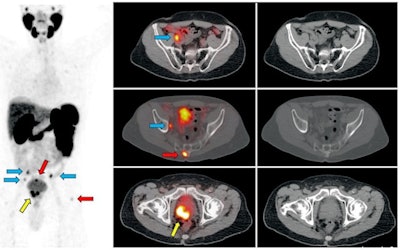

As for interpreting Ga-68 PSMA-11 PET results, the technique "does require proper training, but can be considered easy in comparison to other techniques," UCLA's Calais said. "We have shown in some papers that after 30 to 50 images, one can reach a very decent level of expertise in reading. The interreader reproducibility also is very high, because of the very high, black-on-white contrast imaging. It is more clear-cut than other metabolic tracers that show the activity of the cell."

"There is ample information for the nuclear medicine physicians and radiologists to interpret these [images]," added Sunderland, who also serves as vice chair of SNMMI's Research and Discovery Domain. "There is a different physiological uptake pattern and certain things we need to look for in order not to be misled by certain findings. Because it is so specific, this is not a particularly difficult agent to interpret clinically. That being said, we always need to educate our clinicians on the nuances associated with it."